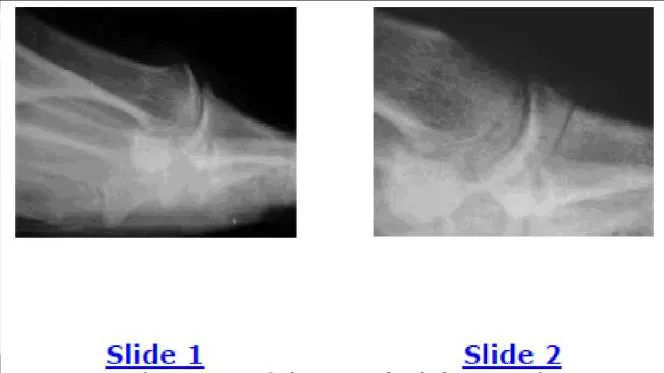

A 38-year-old woman presents for evaluation of painful hallux rigidus. Her clinical and radiographic images are shown (Slide 1 and Slide 2). Based upon her presentation, what is the likelihood that first metatarsus elevatus is responsible for her clinical condition:

Correct Answer: Rare

Explanation:

Surgeons cannot assume that an elevated first metatarsal is responsible for causing hallux rigidus. On a lateral radiograph, there may be notable elevation of the first metatarsal (as present in this patient), but the elevation may be a secondary result of the limited motion of the hallux metatarsophalangeal joint. Studies have demonstrated that there is no difference in the elevation of the first metatatarsal in patients with hallux rigidus.

The patient shown in Slide 1 and Slide 2 underwent surgical correction of painful hallux rigidus. The purpose of the procedure on the hallux was:

- To change the kinematics of the hallux MP joint, thereby decreasing the likelihood of recurrent deformity

Correct Answer: To elevate the hallux off the ground

The osteotomy of the proximal phalanx of the hallux (the Moberg osteotomy) is designed to elevate the hallux off the ground. The procedure does not improve the range of motion of the MP joint, but it increases the available motion of the hallux in toe off.